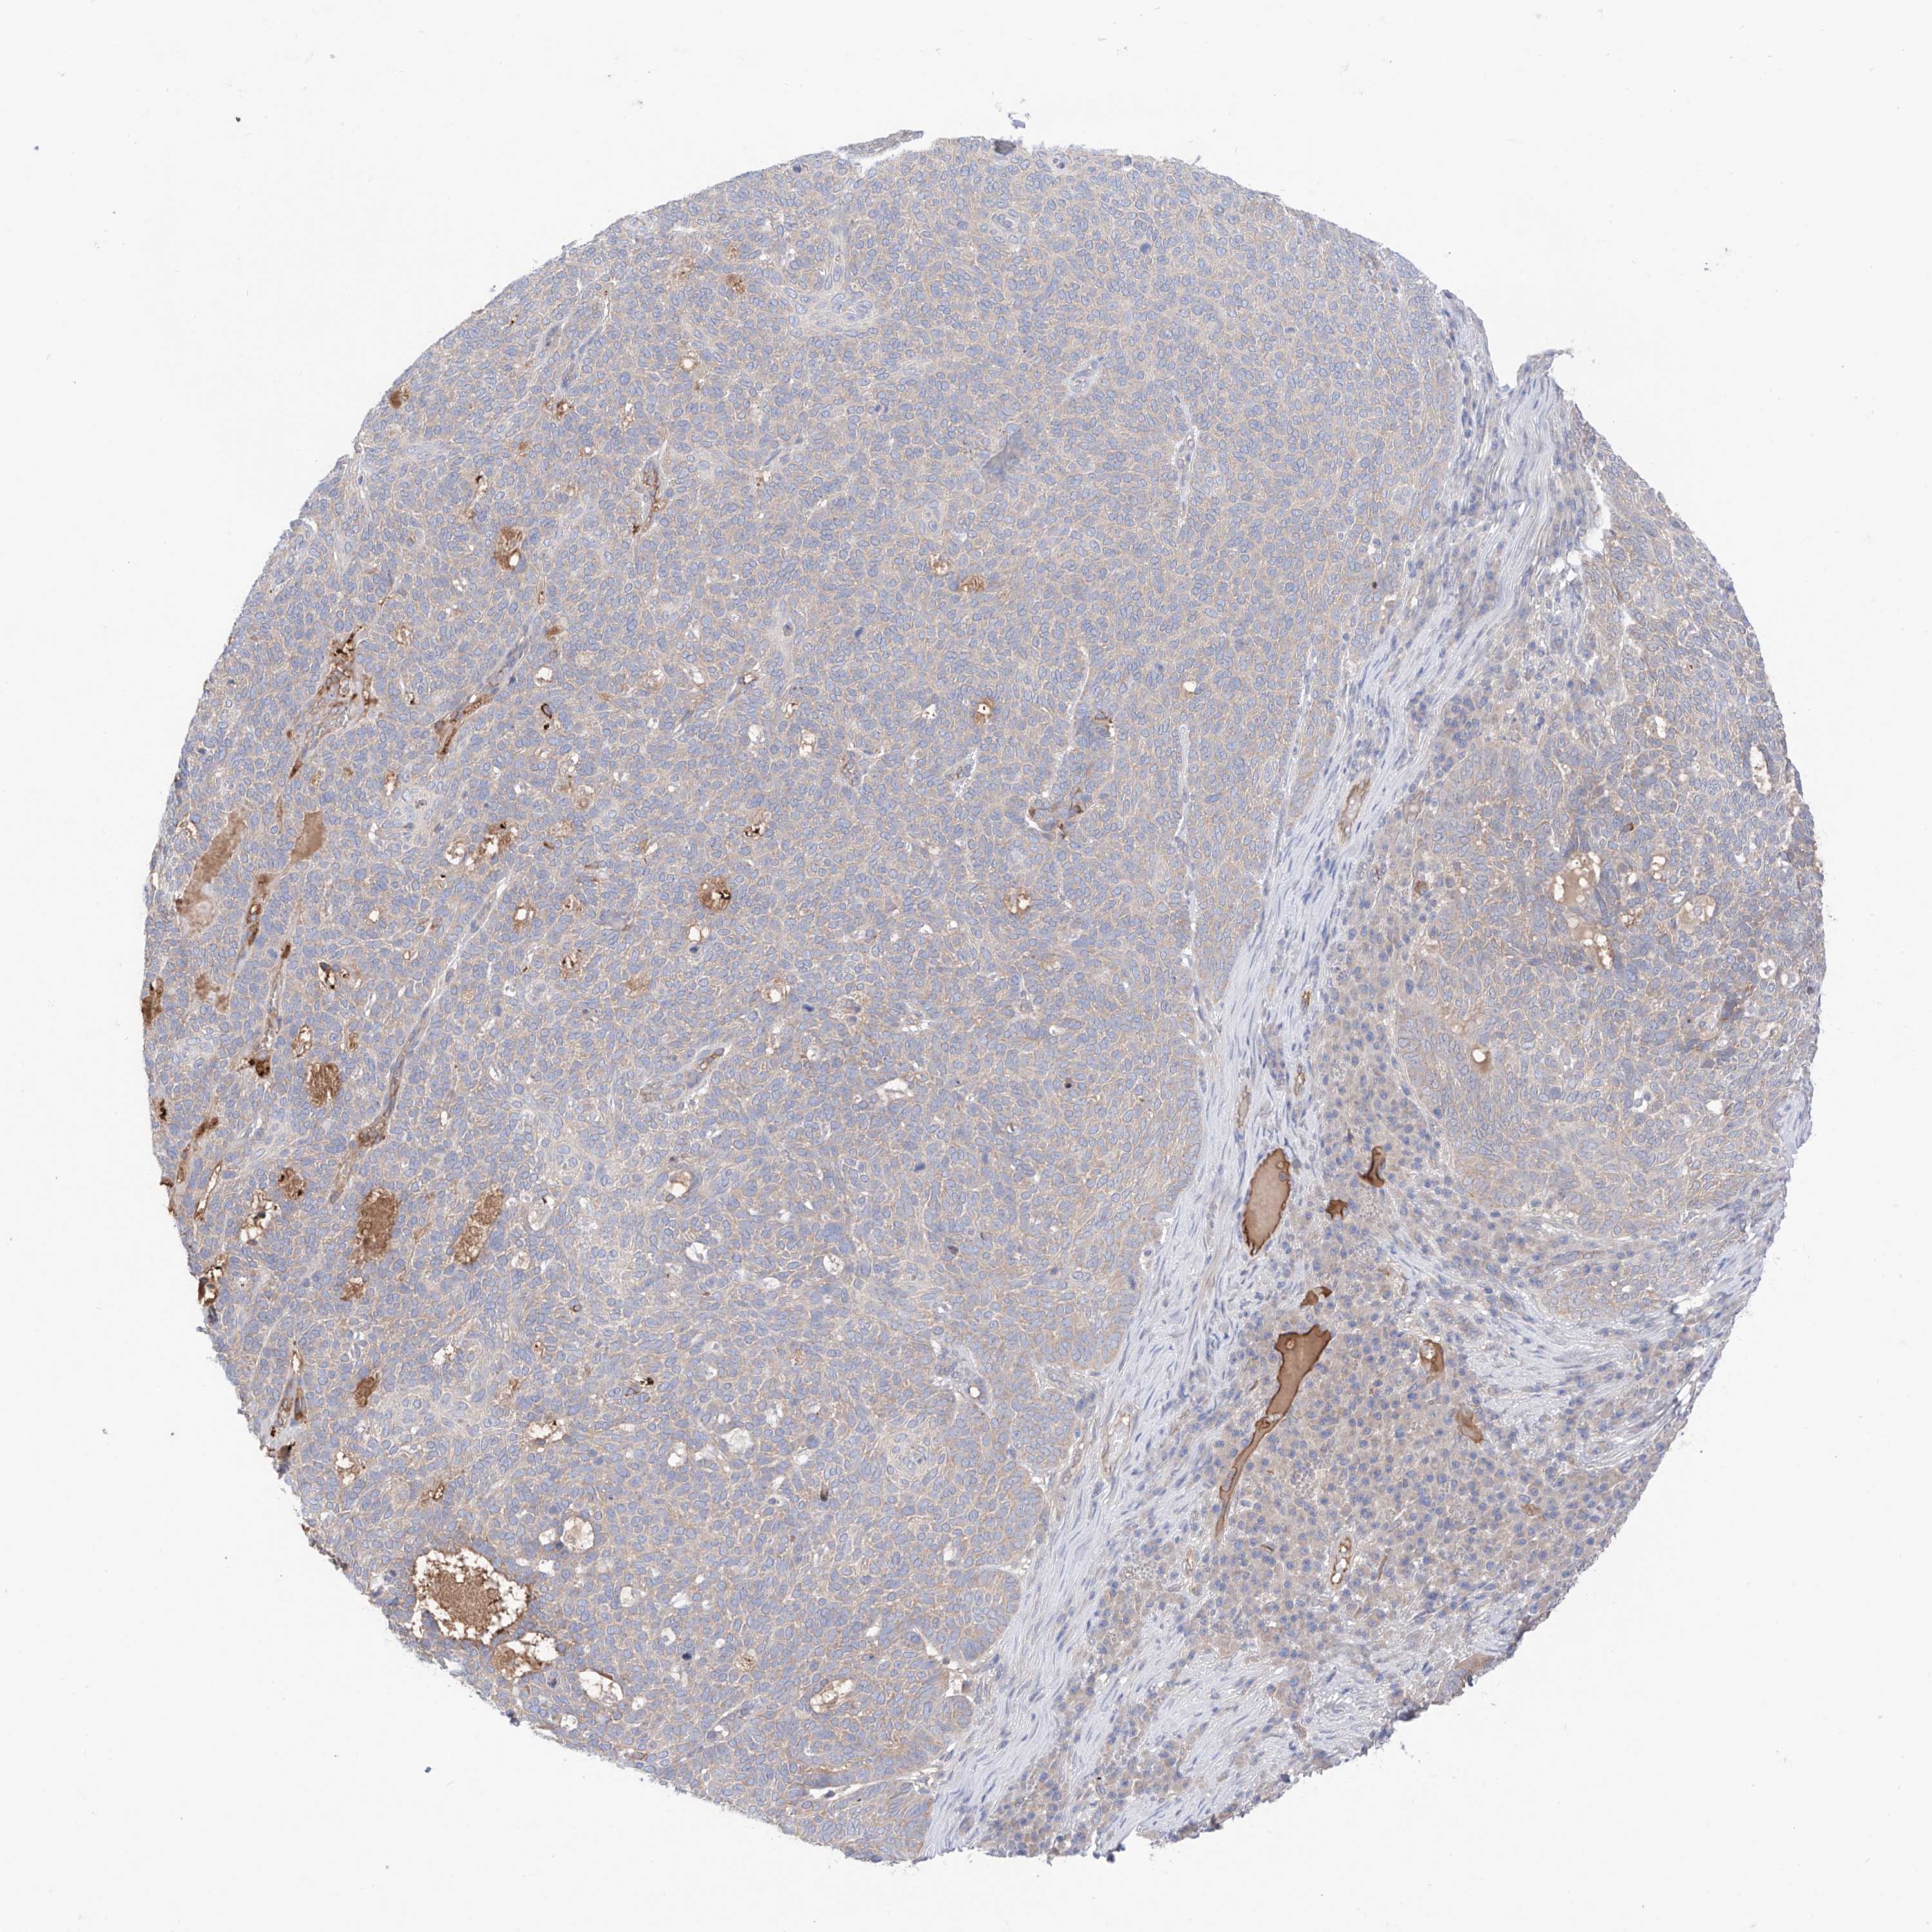

SKIN CANCER - Protein expressioni

A mouse-over function shows sample information and annotation data. Click on an image to view it in a full screen mode. Samples can be filtered based on level of antibody staining by selecting one or several of the following categories: high, medium, low and not detected. The assay and annotation is described here.

Antibody stainingi

Antibody staining in the annotated cell types in the current human tissue is reported as not detected, low, medium, or high, based on conventional immunohistochemistry profiling in selected tissues. This score is based on the combination of the staining intensity and fraction of stained cells.

Each image is clickable and will lead to virtual microscopy that enables deeper exploration of all samples and also displays staining intensity scores, fraction scores and subcellular localization as well as patient and tissue information for each sample.

Antibody HPA030646

Staining

High

Medium

Low

Not detected

Intensity

Strong

Moderate

Weak

Negative

Quantity

>75%

75%-25%

<25%

None

Location

Nuclear

Cytoplasmic/membranous

Cytoplasmic/membranous,nuclear

Squamous cell carcinoma, NOS